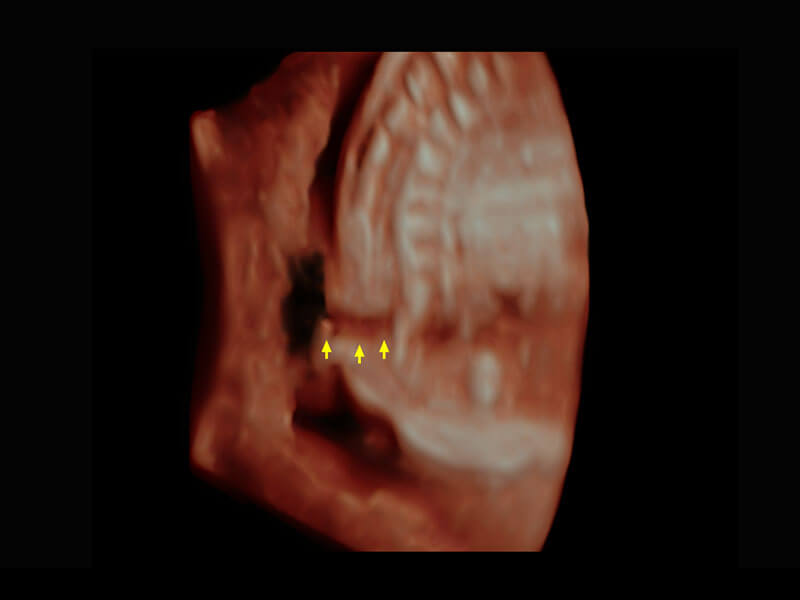

• 腔内三维-宫内节育器

• 腔内三维-光影成像